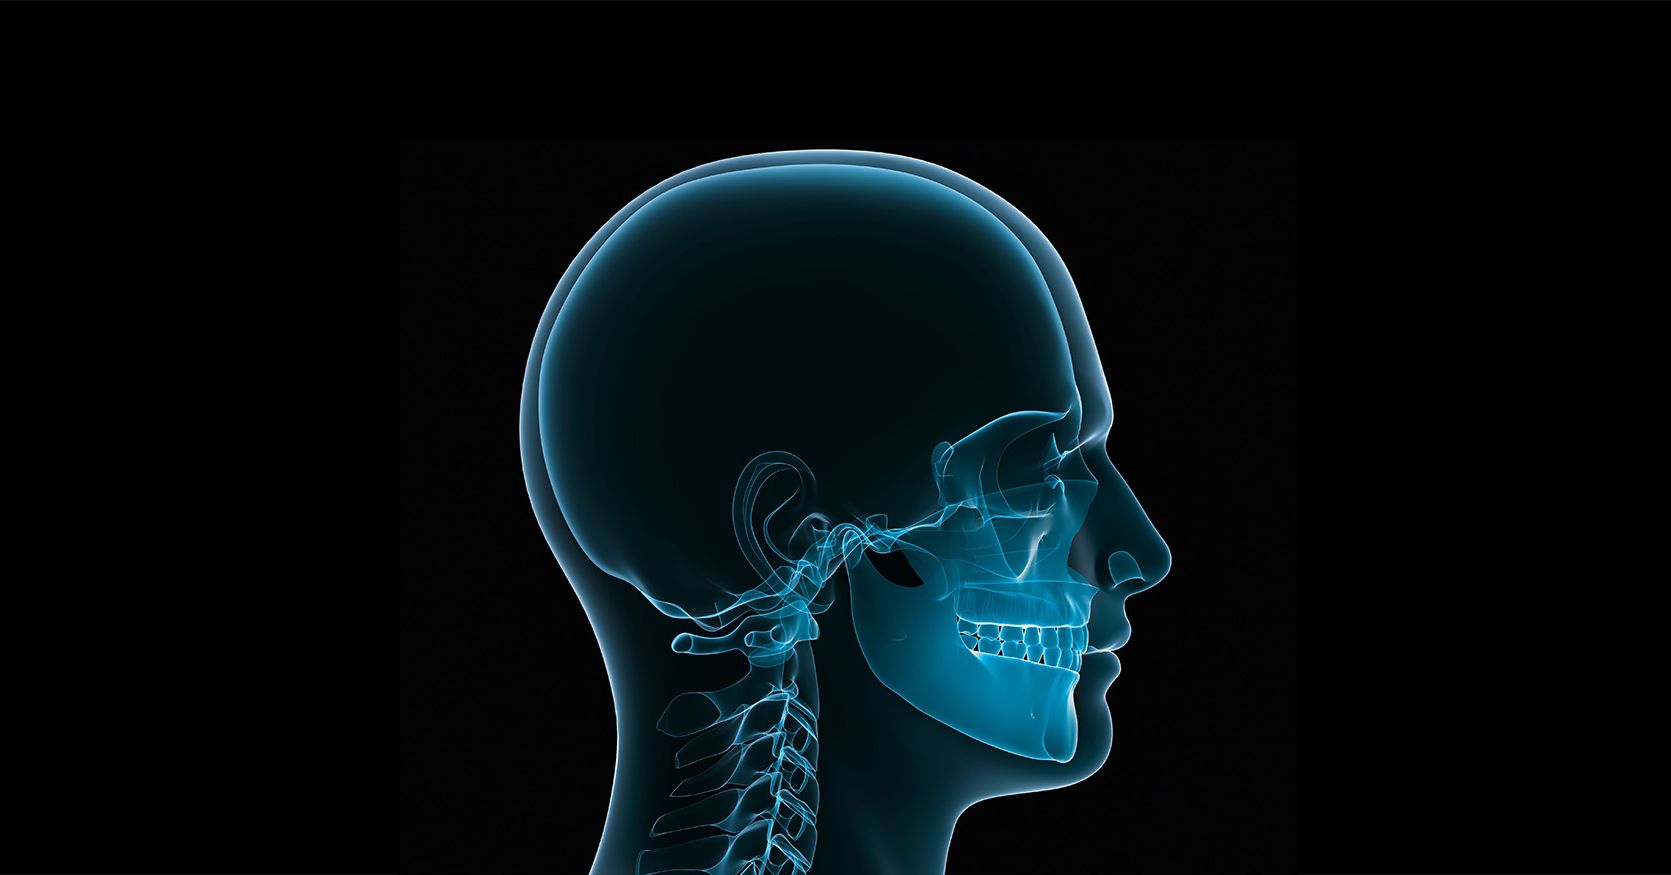

第四版 口腔外科学 华西口腔医学院高举伟大旗帜建世界一流口腔医学学科-中国共产党四川の詳細情報

华西口腔医学院高举伟大旗帜建世界一流口腔医学学科-中国共产党四川。KLS Martin | 牙科和口腔外科。口腔外科- 治疗内容| 松本齿科大学银座八丁目诊所| 种植牙、牙齿矫正。口腔外科学の最新知識を網羅した第4版。。恭喜我们的学生四川大学口腔医学本科录取!学生和ELIC指导老师都超级棒。- タイトル: 口腔外科学 第4版- 著者: 白須秀光- 出版社: 医歯薬出版株式会社- 英語タイトル: Oral and Maxillofacial Surgery- ISBN: 9784263445833ご覧いただきありがとうございます。入門 アーユルヴェーダ アーユルヴェーダ研究会監修 平河出版社1990年